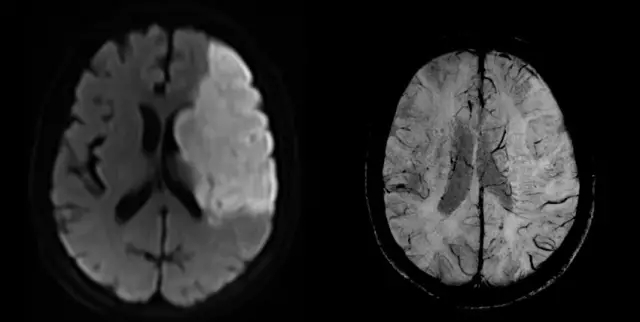

肛瘺應(yīng)用

在肛瘺診療領(lǐng)域,中醫(yī)外科手段輔以中藥治療獨(dú)具特色,如何精準(zhǔn)判斷肛瘺或膿腫的位置、形態(tài)、走向及其與肛管直腸、肛門括約肌及肛提肌的關(guān)系,對治療起到關(guān)鍵性作用。聯(lián)影中醫(yī)磁共振搭載專用掃描協(xié)議和創(chuàng)新性序列技術(shù),可清晰顯示內(nèi)口、在任意方向重建肛瘺形態(tài)、清晰顯示炎癥血管。

聯(lián)影醫(yī)療發(fā)布業(yè)界首臺中醫(yī)磁共振成像系統(tǒng)

各項(xiàng)同性成像序列技術(shù)(quick 3D)可在任意方向重建肛瘺形態(tài),多維度顯示瘺口,觀測復(fù)雜肛瘺走形,通過最大密度投影重建清晰顯示炎癥血管。